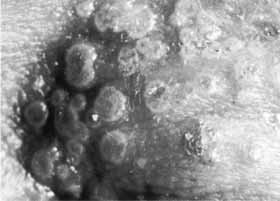

Although viral particles have been demonstrated by electron microscopy within the corneal stroma in cases of stromal herpes simplex keratitis55–57 (Figs. 22 and 23), attempts to isolate infected virions in tissue culture have been successful in only a minority of cases. In most cases of stromal herpes simplex keratitis, the clinical disease appears to be predominantly the result of an immunopathologic process, which is a response to viral antigen rather than an active infectious process caused by replicating virus. Immunocytochemical studies of cornea tissue obtained from patients with herpes simplex stromal keratitis at the time of penetrating keratoplasty have shown the stromal infiltrate to be composed largely of macrophages and lymphocytes.58 Controversy exists as to whether cytotoxic or helper T cells play the major role in herpetic keratitis.58

Fig. 22 Electron micrograph of deep corneal stroma. Numerous Herpesvirus particles can be seen lying in and around two degenerate cells (probably keratocytes) between stromal lamellae. (Magnification × 16,000) (Courtesy of Dr. R. Tripathi).

Fig. 23 Electron micrograph of keratocyte. This degenerating cell is filled with Herpesvirus particles. Some of these have typical morphology (arrow). Note the number of incomplete forms, empty capsids and great variability in size (arrow). (Magnification × 100,000) (Courtesy of Dr. R. Tripathi).